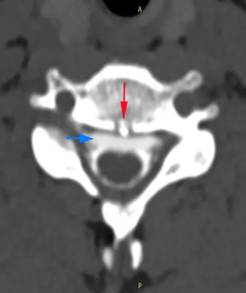

小江的脊柱磁共振检查可见第1、2胸椎之间有“骨刺”形成(红箭头)刺破硬脊髓膜,造成脑脊液外漏(蓝箭头)医院供图